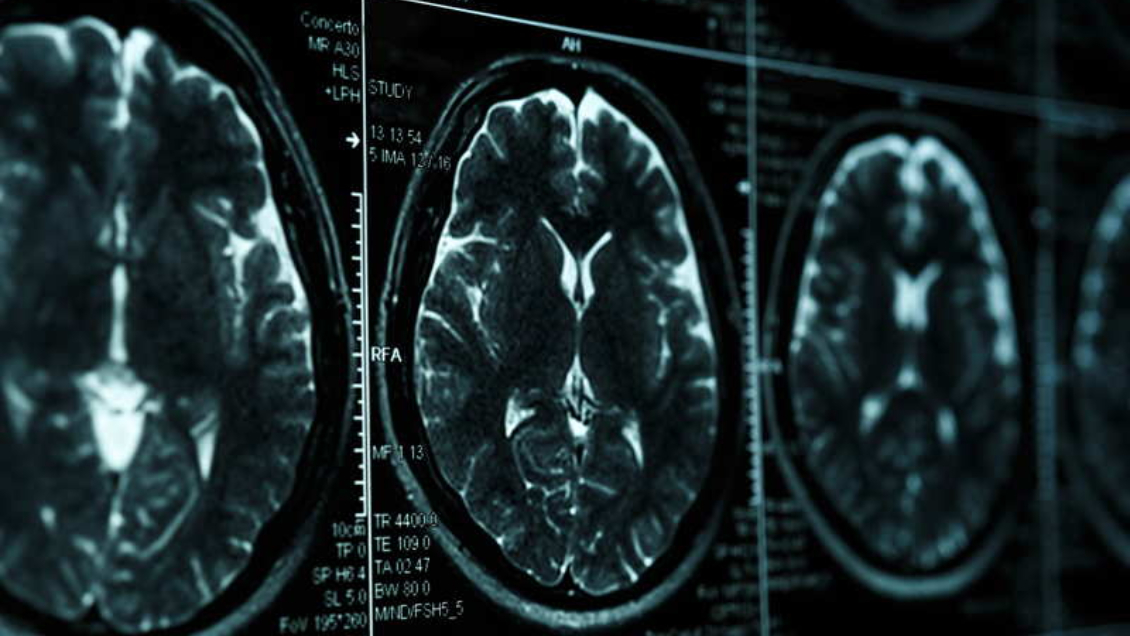

Un equipo de expertos de Pekín informaron del "probable" primer caso de un adolescente de 19 años con la enfermedad de Alzhéimer y confirmaron que la dolencia no es exclusiva de personas adultas o ancianas.

Según el grupo de científicos del Centro de Innovación para Desórdenes Neurológicos de un hospital pequinés, el joven empezó a sufrir problemas de memoria a los 17 años y dificultades de concentración en sus estudios.

Un año más tarde ya padecía una "pérdida significativa de memoria reciente" que le impedía recordar eventos del día anterior o dónde estaban guardadas sus pertenencias.

Su capacidad lectora se vio mermada y sus reacciones empezaron a ser cada vez más lentas, indicaron los expertos.

El declive gradual de su memoria se agravó hasta el punto de que no podía recordar si había comido o no y, como resultado del deterioro de sus funciones, el paciente tuvo que abandonar la escuela secundaria.

Jia Jianping, que lideró el estudio, aseveró que no había un historial de Alzhéimer en la familia del joven y este tampoco tenía problemas genéticos o enfermedades que pudiesen ser la causa de la pérdida de memoria.

Jia pidió más atención a la posibilidad de que el Alzhéimer se manifieste en personas jóvenes.